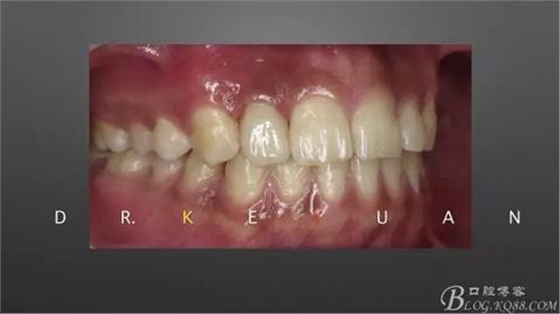

10、復(fù)診試戴最終修復(fù)體(又爭取了2周的時間,再加上技師對最終修復(fù)體鄰接關(guān)系的設(shè)計,牙齦恢復(fù)效果明顯)

11、牙齦狀況對比(有時候你把患者約的時間太長,他可能會不理解你,約著約著就再也約不過來了,有些時候患者的修復(fù)熱情和臨床的治療程序可能成反比,我們要做金玉其外、金玉其中的修復(fù),實難取舍)

12、粘接后即刻(齦緣的高度略有差異,這應(yīng)該可以說明冠延長術(shù)和正畸牽引的效果差異)

13、術(shù)前術(shù)后對比